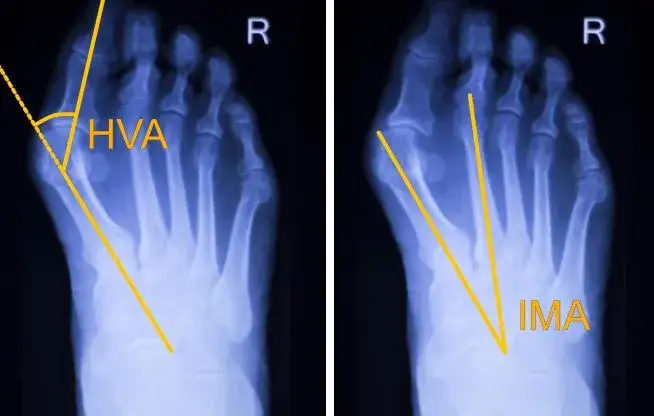

Haluksy: Co to jest? Przyczyny, objawy i skuteczne leczenie.

Haluksy: Co to jest paluch koślawy? Poznaj przyczyny, objawy i skuteczne metody leczenia od zachowawczych po operacyjne. Sprawdź nasz przewodnik!